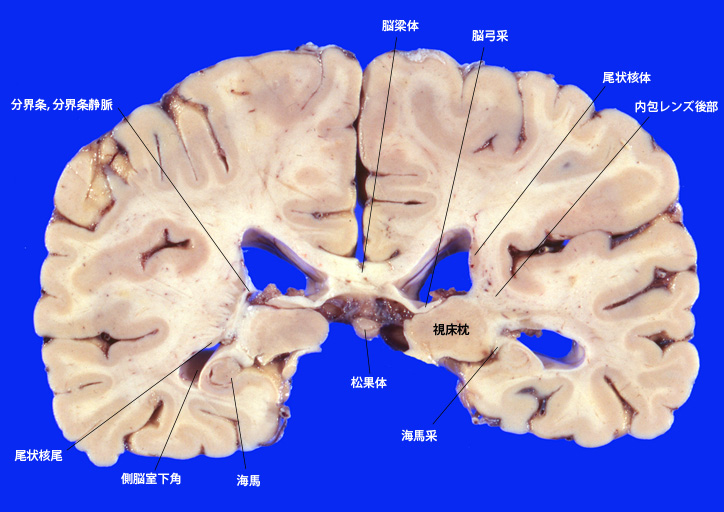

3. 視床内外膝状体、視床枕をとおる断面

4. 松果体の認められる断面